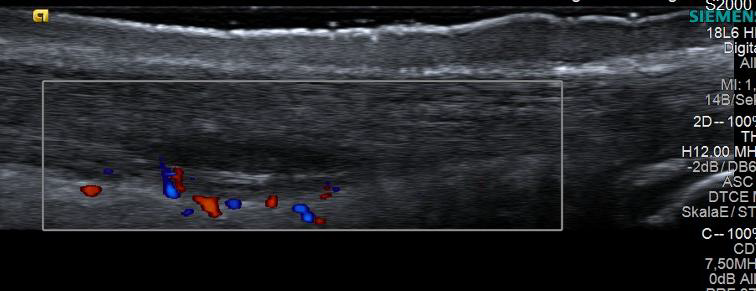

Die Sonographie folgt stets einer vorausgehenden klinischen Untersuchung. In diesem Fall Vorliegen einer akuten Mid-Portion Tendinopathie der Achillessehne mit spindelförmiger Auftreibung, echoarmer ventraler Raumforderung und Zeichen einer Hypervaskularisation im Farbdoppler (Kasten). © Hotfiel.